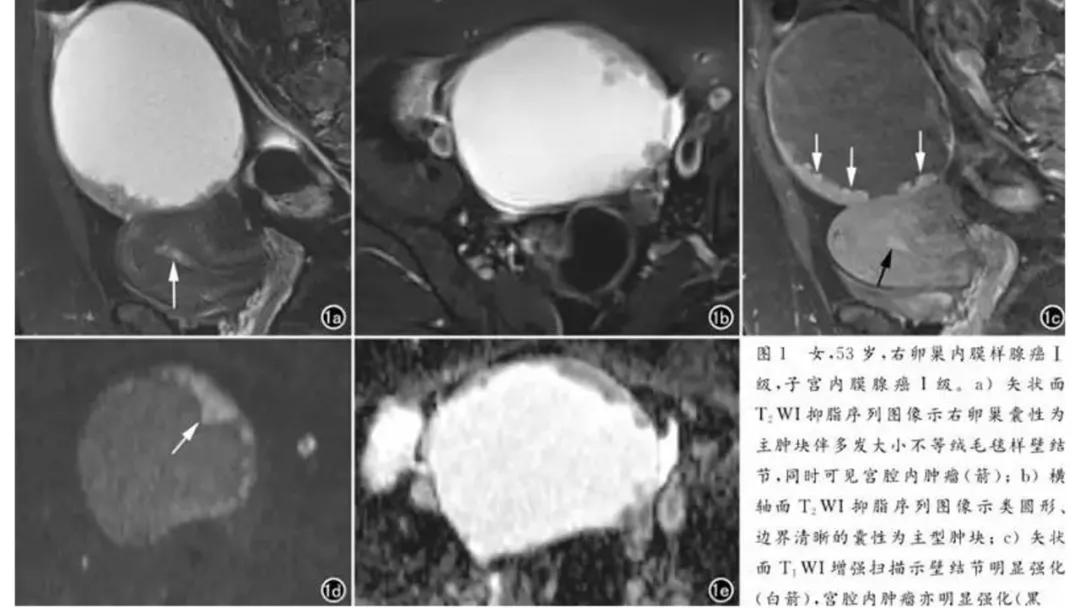

上皮性肿瘤:最常见,恶性多(卵巢癌),良性少。好发于50Y以上,发现时多为中晚期。多呈囊性或以囊性为主的囊实性肿块,完全实性者少见。形态多数不规则,边界模糊,囊壁及房间隔常不规则增厚,菜花样肿物或壁结节,囊实性区域分界不清,实性肿瘤常有不规则低密度或坏死区,可有边界模糊沙粒状或块状钙化,中-高度强化。良性者边界清晰,囊壁薄光整,无壁结节,实性部分呈无或轻度强化。